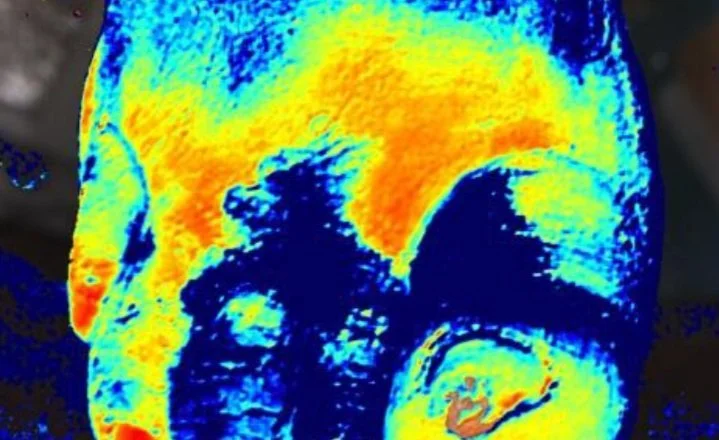

In a series of educational-based live webinars, Kent’s CMO, Dr. Jeffrey Niezgoda, takes audiences through clinical scenarios and image interpretation with Kent Imaging’s near-infrared spectroscopy device, SnapshotNIR.

The use of imaging devices to capture focused wound data, known as wound image informatics. Dr. Niezgoda and guest, Dr. Travis Hubbuch, will also review near-infrared spectroscopy imaging across multiple devices, showing that not all NIRS technology is the same.

Dr. Jeffrey Niezgoda and Dr. Glyn Jones, discuss SnapshotNIR’s unique hemoglobin view, applications in wound care, vascular and surgery, and the new SnapshotNIR update with advanced melanin features.

EPISODE 7: Using Near-Infrared Spectroscopy to Visualize and Evaluate Angiosomes

Using SnapshotNIR and the correlation of NIRS imaging to foot and ankle angiosomes with corresponding case studies with guest, Erin Buchness